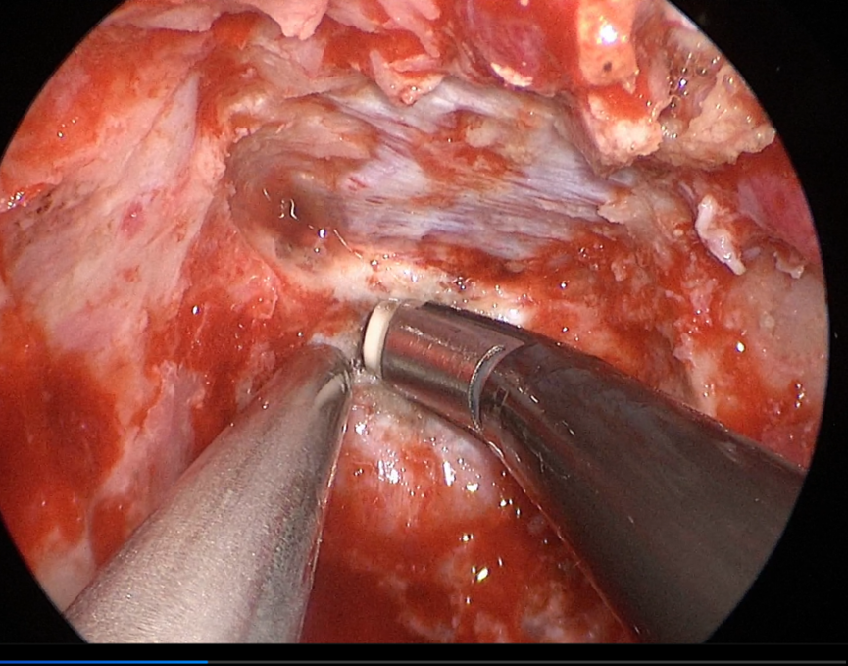

自近蝶窦前壁处向左侧推挤鼻中隔,离断筛骨垂直板,咬除部分近蝶窦处骨性鼻中隔,分离双侧鼻粘膜显露蝶窦前壁,自蝶窦开口上方做沿鼻中隔做粘膜瓣备用,末端到中鼻甲位置,将粘膜瓣压向下鼻道,高速磨钻磨除蝶窦下壁骨质,鞍结节骨质。术中视神经管清晰可见,给予保护,海绵间窦出血给予流体明胶+凝血酶止血;等离子刀一边止血一边切开硬脑膜见白色肿瘤质韧,边界清晰,大脑前动脉分支粘连于肿瘤表面,给予小心分离,以刮圈,咬切钳等小心清除肿瘤组织;内镜下将肿瘤完整切除;取右侧大腿皮下脂肪及阔筋膜备用,以人工硬膜修补和明胶海绵封闭鞍底硬膜,将脂肪放置于切口,并缝合于鞍底硬脑膜上固定铺平,阔筋膜覆盖于脂肪外边,蝶窦内充填明胶海绵止血,鼻粘膜瓣覆盖于蝶窦;碘仿纱条填塞鼻腔;护士清点棉条、器械、纱布无误,撤出鼻镜。